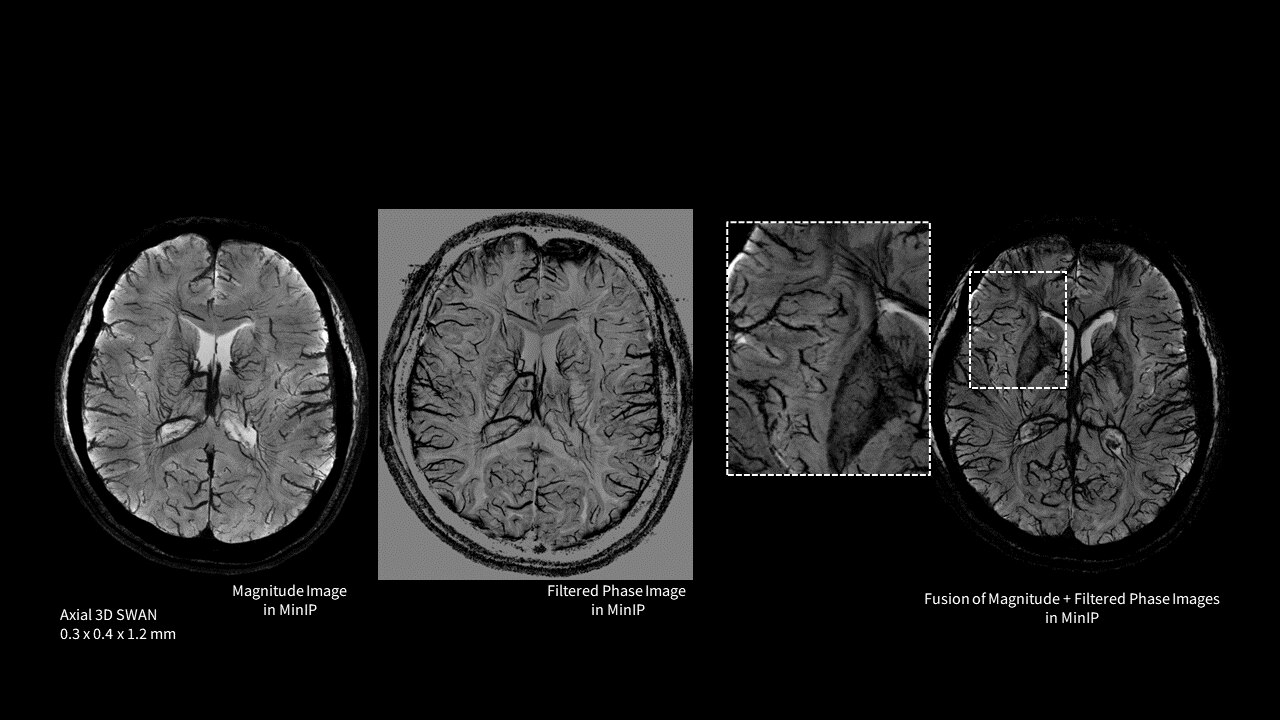

Phase and magnitude images to visualize iron and calcium deposits

Multi-TE readout technique generates more than double signal-to-noise ratio

SWAN helps delineate small blood vessels, microbleeds, and large vascular structures in the brain. It applies a multi-TE readout technique that generates more than double SNR and is inherently less affected by the chemical shift compared to conventional SWI techniques. Whole brain acquisition with 3D, sub-millimeter resolution takes ~4 minutes—image reconstruction is virtually instantaneous.